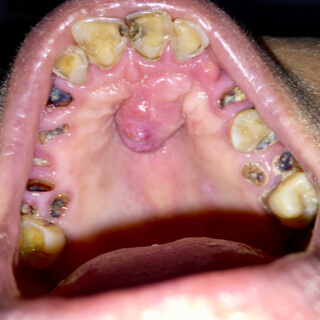

3. كتل على الفك

تظهر هذه الكتل غالبًا في سقف الفم أو على طول خط اللثة، وقد يكون الشعور بوجود كتلة أو ظهورها علامة على تطور السرطان في عظام الفك الموجودة أسفل الأنسجة الرخوة في الفم، ومن المفترض في حال الشعور بوجودها وعدم غيابها مراجعة الطبيب للتأكد من نوعها، فقد تكون ناتجة عن إصابتك بعدوى ما أو قد تكون ورمًا حميدًا ويمكن حلّه.

أعراض سرطان الحلق الصلب

يعرف هذا النوع من سرطان الفك بسرطان الحلق الصلب، يمكن الكشف عنه بسهولة من خلال الأعراض المصاحبة له ومن أبرزها:

• قرحة في سقف الفم.

• بقعة حمراء أو بيضاء على سقف الفم.

• انتفاخ سقف الفم.